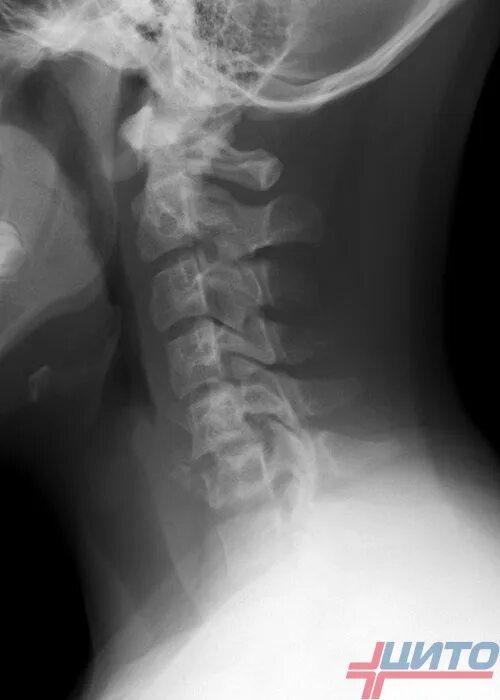

Экзостоз мкб 10